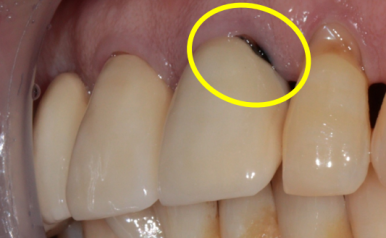

보철물 경계부에 생기는 2차 우식

(좌측: 다른 환자분의 케이스)

(우측: 이번 케이스 환자분의 아래 치아)